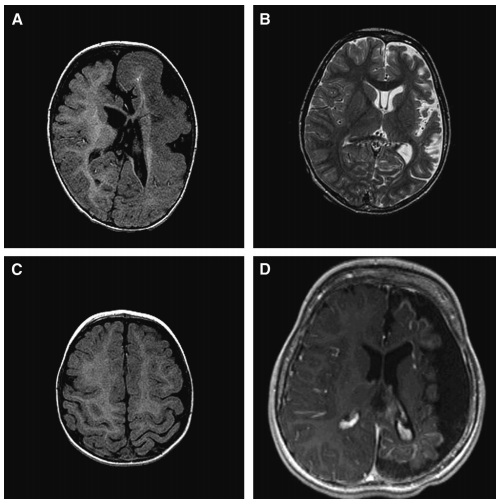

图示:儿童大脑半球异常引起灾难性癫痫的磁共振成像(MRI)。A,轴向t1加权MRI的12个月的男性患者顽固性癫痫显示左半脑畸形。注意左半球的体积比右半球大,中线结构向右偏移。B,轴向t2加权MRI的5岁男孩顽固性左半球癫痫。注意萎缩的左半球,脑脊液腔增大。较后的诊断是拉斯姆森脑炎。C ,1月龄男性顽固性右半脑癫痫患者的轴位t1加权MRI。广泛的皮质发育不良是建议的MRI扫描和被证实的组织病理学检查。D,轴向t1加权MRI钆显示萎缩左半球与软脑膜增强在这个3岁的孩子。诊断为斯图格-韦伯综合征合并软脑膜血管瘤病。